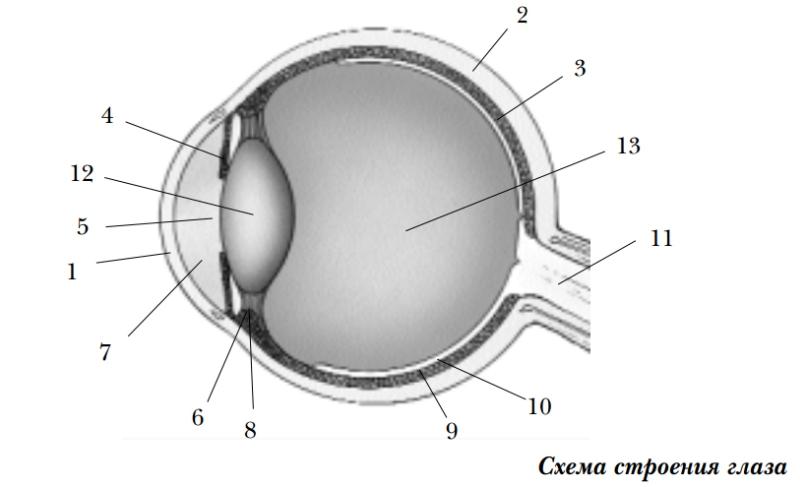

КТ-графики и изображение строения глаза